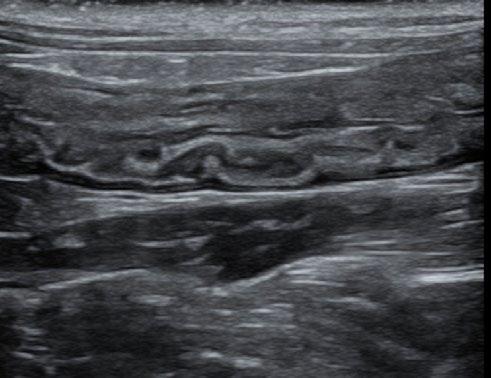

A repeat ultrasound after 10 days of treatment indicated early evidence of a reduction of the colonic lesion.

We planned to provide 42 days of treatment and serially assess the lesion by ultrasound to determine the effect of the treatment.

Here are the sequential images:

At the time of writing, 1 month after completion of a 42 day course of medication, Cha Cha is asymptomatic, with no clinical, clinical pathological, or sonographically detectable signs of disease. This response is very difficult to attribute to anything other than highly effective treatment of focal, colonic ‘dry’ FIP with GS-441524.